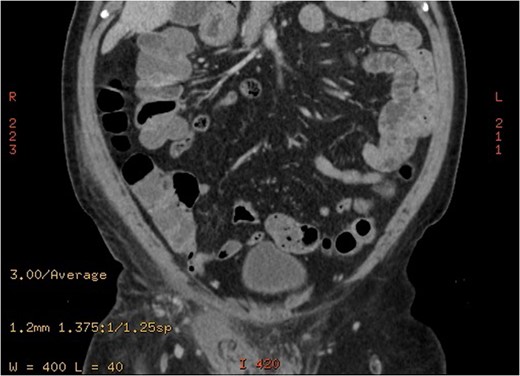

A 63-year-old gentleman who is a known case of dyslipidemia was presented to our Emergency Department with a right sided scrotal swelling and pain for 1 week. The patient had been having right testicular pain for the past 6 months on and off but never sought medical advice. On clinical examination, the patient had right scrotal swelling with epidydimal and cord tenderness and swelling, the cremasteric reflex could not have been assessed due to the large size of the scrotum with reactive scrotal wall edema. The patient underwent Doppler ultrasound which showed right testicular heterogeneous echotexture with nodular hypo-echoic areas (Fig. 1) with preserved vascularity. There was no evidence of testicular torsion or masses in that study. A provisional clinical correlation was made and the patient was diagnosed with right epididymo-orchitis and discharged home on oral antibiotics. Next day, the patient presented again to our ER with increased pain, swelling and erythema reaching the right inguinal area. So, the patient was admitted for administration of intravenous antibiotics. After 2 days of IV antibiotics, the patient’s condition was not improving which prompted the need of a CT scan. CT scan showed a heterogeneous enlarged right testis with twisting of the spermatic cord at the level of inguinal area and scrotal neck (Fig. 2). A diagnosis of testicular torsion was made based on these findings. The patient then underwent an urgent exploration with an inguinal incision which showed a hugely edematous cord, the incision was extended as Hockey-Stick incision and the right testis was delivered. The testis was dark, edematous, with no evidence of palpable testicular masses. The spermatic cord was twisted in 1080° clockwise fashion in three areas (Fig. 3). The first 360°, torsion was at the level of the deep inguinal ring, the second at inguinal part of the spermatic cord, and the third is just proximal to the testis. Right radical orchiectomy was carried out with high ligation of the spermatic cord at the level of deep inguinal ring, which was the site of normal, non-engorged cord. The procedure was completed with the extended inguinal incision with no violation of the scrotum, since the pathology was high in the inguinal area. The patient recovered very well with no complications.

A coronal cut of and enhanced abdominal CT scan showing enlarged right spermatic cord and areas of decreased right testicular enhancement suggesting torsion.